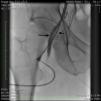

An angiogram from the left femoral sheath at this time showed retrograde filling of the distal and proximal SFA (Figure 4) and then the dissection plane in the EIA with a wire tip perforation and bleeding (Figures 5 and 6) to the retroperitoneal region at the external iliac artery with displaced bladder (Figure 6). Protamine was given to reverse the heparin and a 7-minute balloon inflation was performed in the distal SFA using a 5.0 mm×40 mm Evercross balloon (ev3, Plymouth, MN) to stop the retrograde bleeding. On repeat angiography, the distal SFA CTO was reoccluded and the dissection plane appeared to be sealed, with no further bleeding into the retroperitoneal region (Figures 7 and 8). Other than mild nausea after protamine, the patient reported no major symptoms during this procedure. When activated coagulation time was 130 s, the femoral and popliteal sheaths were removed. A 3-g/dl drop in hemoglobin was noted after the procedure that remained stable over the next two days. Popliteal and pedal pulses were palpable and unchanged following the procedure.